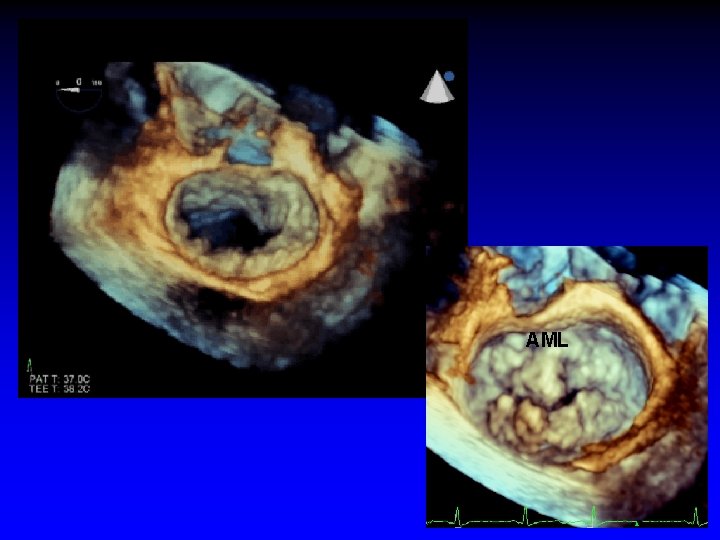

AML